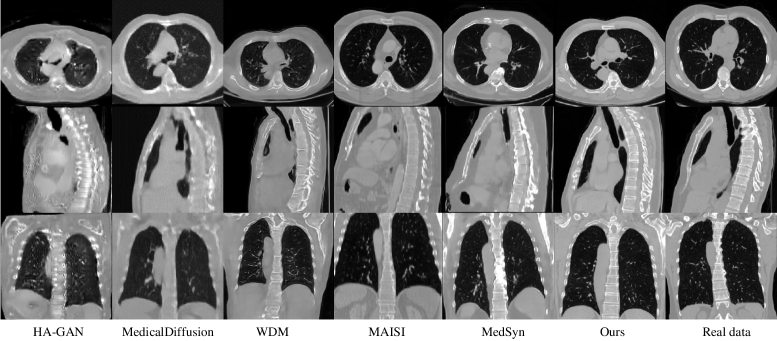

To qualitatively evaluate the generation capabilities of all methods, we present some generated samples from CTChestAbdomen dataset (Fig. 4) and MRBrain dataset (Fig. 5). It is evident that HA-GAN, MedicalDiffusion, and WDM struggle to produce high-resolution CT images, resulting in noisy and blurry outputs with insufficient details. MAISI and MedSyn produce satisfactory results but are slightly inferior to our method. In contrast, our proposed method excels in capturing fine details like vertebrae in CT images. It also produces sharp edges, such as the brain surface of MR images.